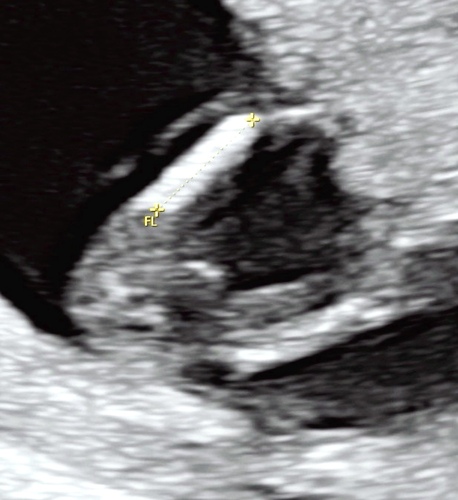

Iemand enig idee wat we hier zien? 💙💗 gisteren mijn 13 weken echo gehad! Ben zo mega benieuwd! Een klein gokje is altijd leuk, 10 februari de geslachtsecho